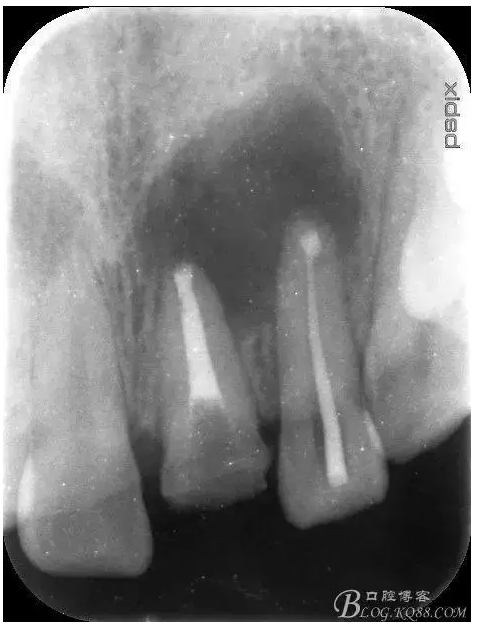

轉:張東星 愛齒-KQ88口腔醫(yī)學